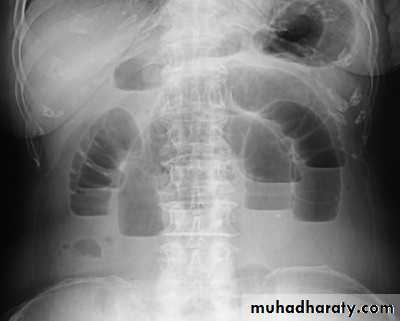

Imaging studies:

plain X ray of the abdomen

CXR in erect position.

U/S and/or CT Scan.